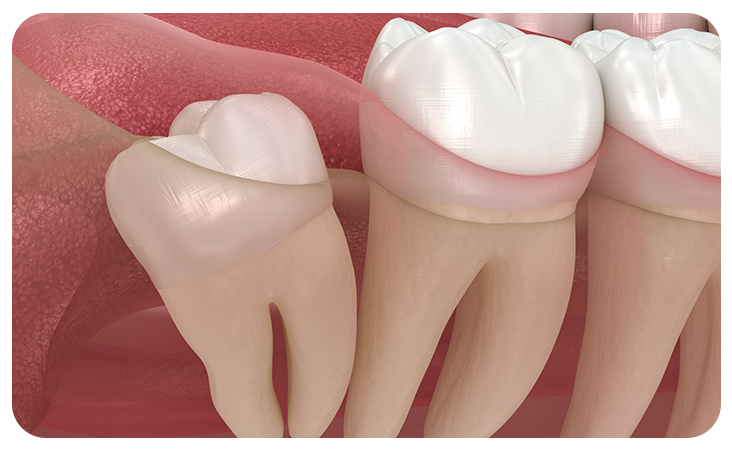

매복사랑니란?

사랑니가 완전히 맹출 되지 않고 잇몸 아래에 묻혀있는 형태의 사랑니를 매복 사랑니라고 합니다.

매복 사랑니는 함치성낭종, 염증 유발, 턱뼈 손상 등의 문제를 유발할 수 있어 발치해주는 것이 좋습니다.

수직매복

수평매복

부분매복

원심경사 매복